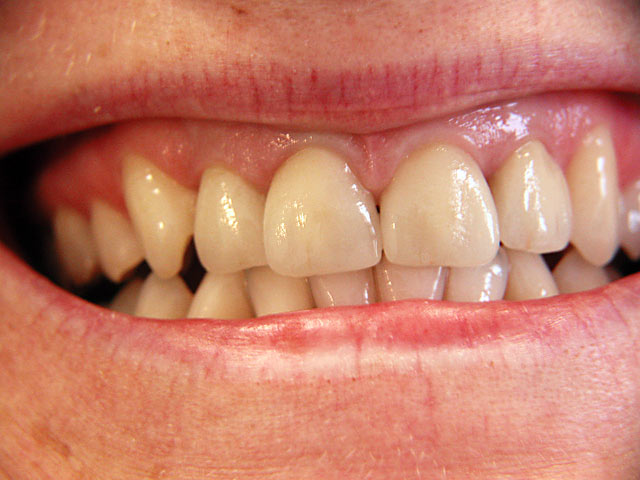

Die folgenden Patientenfälle sollen Ihnen einen Einblick in die Möglichkeiten der modernen Implantation geben.

Implantation – Patientenbeispiel 2: